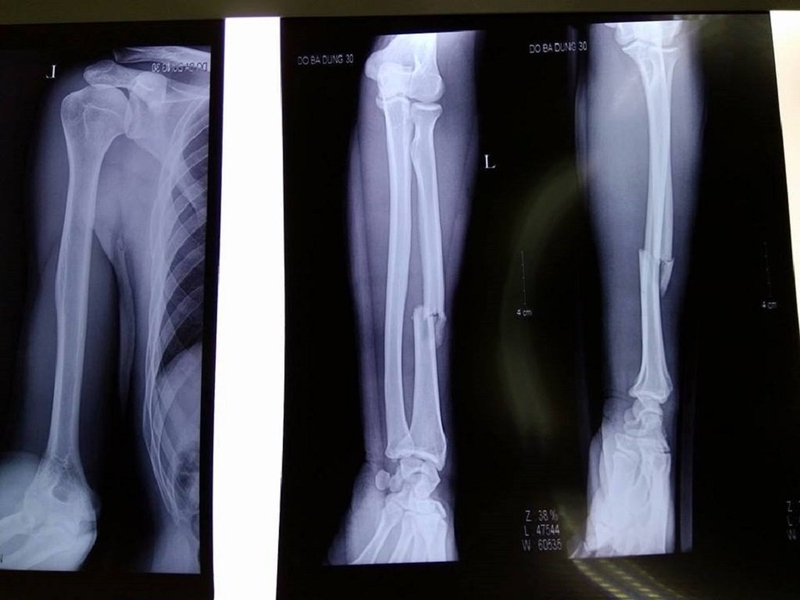

Nhiều nguyên nhân có thể dẫn đến tình trạng rạn xương trụ như chấn thương do ngã, va đập hoặc áp lực từ vật nặng.

Trong trường hợp rạn, cánh tay có thể không biến dạng nhưng vẫn gây đau đớn và đòi hỏi người bệnh cần xử lý kịp thời. Tình trạng nghiêm trọng hơn là khi xảy ra gãy, đầu gãy có thể đâm vào da hoặc tạo ra trạng thái trật khớp.

Khi bị gãy xương trụ có một số dấu hiệu điển hình để nhận biết bao gồm: